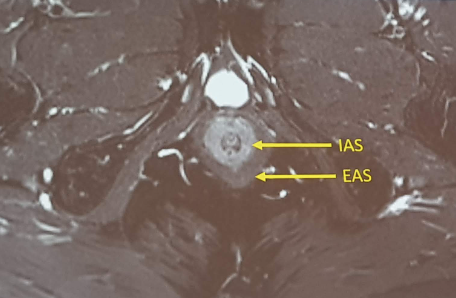

ANATOMIA DEL CANALE ANALE:

- SFINTERE ANALE INTERNO (IAS)

- SFINTERE ANALE ESTERNO (EAS)

La risonanza magnetica (RM) è considerata indispensabile nello studio delle fistole anali per diverse ragioni. Ecco i principali punti che rendono la RM una modalità di imaging cruciale per questa condizione:

1. Dettagli anatomici:

La RM offre una visualizzazione dettagliata ,ad elevata risoluzione spaziale e delle strutture anatomiche del pavimento pelvico, in particolare degli sfinteri anali, consentendo grazie anche all’ ottima differenziazione contrastografica delle strutture in esame , di identificare con precisione il percorso della fistola, la sua origine e le sue ramificazioni. Questo è particolarmente importante per la pianificazione chirurgica.